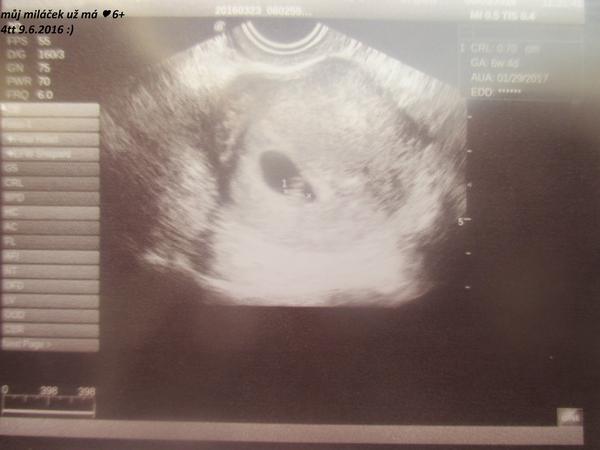

Tak presne takovou tecku jsem tam mela 🙂 takze podle mych lajckych vypoctu budem o tyden mensi,zatim..a gratuluju 🙂

@alelajda Záleží na kvalitě stroje 🙂 Já měla ve 4+1 bublinku. Držím palce